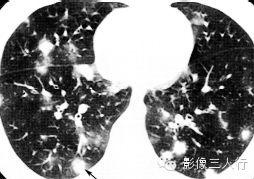

| 病毒性肺炎(图1) | 粟粒性肺结核(图2) | 细支气管肺泡癌(图3) | 肺尘埃沉着病(图4) | 肺泡蛋白沉着症(图5) | 血吸虫病(图6) | |

散在分布,6〜8mm或更小 | 分布均匀,直径1〜2mm | 分布不均,直径6〜7 mm | 分布不均,直径多为2〜5mm | 地图样、铺路石征 | 大小不等,直径多为1〜5mm |

较模糊 | 较清楚或较模糊 | 较清楚 | 较清楚 | 较清楚 | 较模糊 |

病灶密度相同,大小不等 | 病灶密度相同或不同 | 病灶密度相同,呈含气支气管征及蜂窝征 | 病灶密度不均,有钙化 | 磨玻璃密度,地图样分布和铺路石征 | 病灶密度不均,典型者可见晕征 |